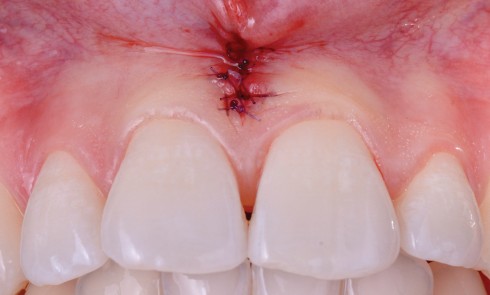

Article réservé à nos abonnés Harmonisation des collets avec allongement de couronnes cliniques

L’esthétique du sourire impose la recherche d’un équilibre entre le parodonte et les dents, d’une harmonie entre le rose et...